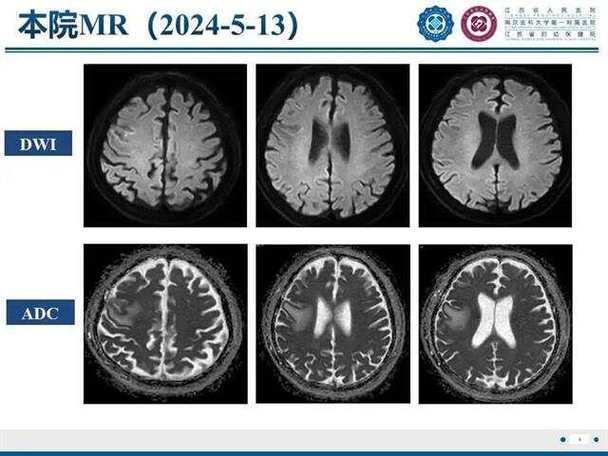

DWI图像上怎么看结果?

在看DWI图像时,我们通常会同时看另一张图像,叫做ADC图 (Apparent Diffusion Coefficient,表观弥散系数图)。

DWI像:

- 正常脑组织:呈中等灰色信号。

- 急性梗死区域:由于水分子运动受限,信号会显著增高,表现为“亮白”的病灶,这是最直观的诊断依据。

-

ADC图:

(图片来源网络,侵删)- 正常脑组织:呈中等灰色信号。

- 急性梗死区域:因为水分子扩散受限,其表观弥散系数值会降低,在ADC图上表现为“变黑”。

简单记忆:

- DWI像上“亮白” + ADC图上“变黑” = 典型的急性脑梗死,这个组合被称为“弥散受限”,是诊断急性脑梗死的标志性表现。

为什么需要ADC图? 主要是为了鉴别,有些其他情况(如肿瘤、感染)在DWI上也可能呈高信号,但ADC图上不一定会变黑,ADC图可以帮助区分急性期和慢性期的梗死。